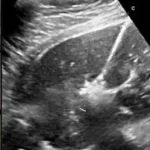

• Ecografia Transvaginale: utilizzata per valutare le caratteristiche del fibroma, come la ipo- o iperecogenicità, la disomogenità e l’irrorazione del tessuto.

Diagnosi dei fibromi uterini tramite tecniche avanzate di imaging